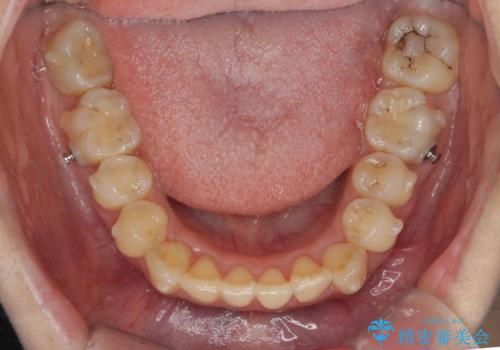

- 20代女性

- インビザライン

- 1年11ヶ月

- 前歯の突出を主訴に来院。

上の奥歯を後ろに下げて治療をしました。

矯正用のミニスクリューを使用しています。

上の前歯もIPR(エナメル質をわずかに削る処置)を行っています。